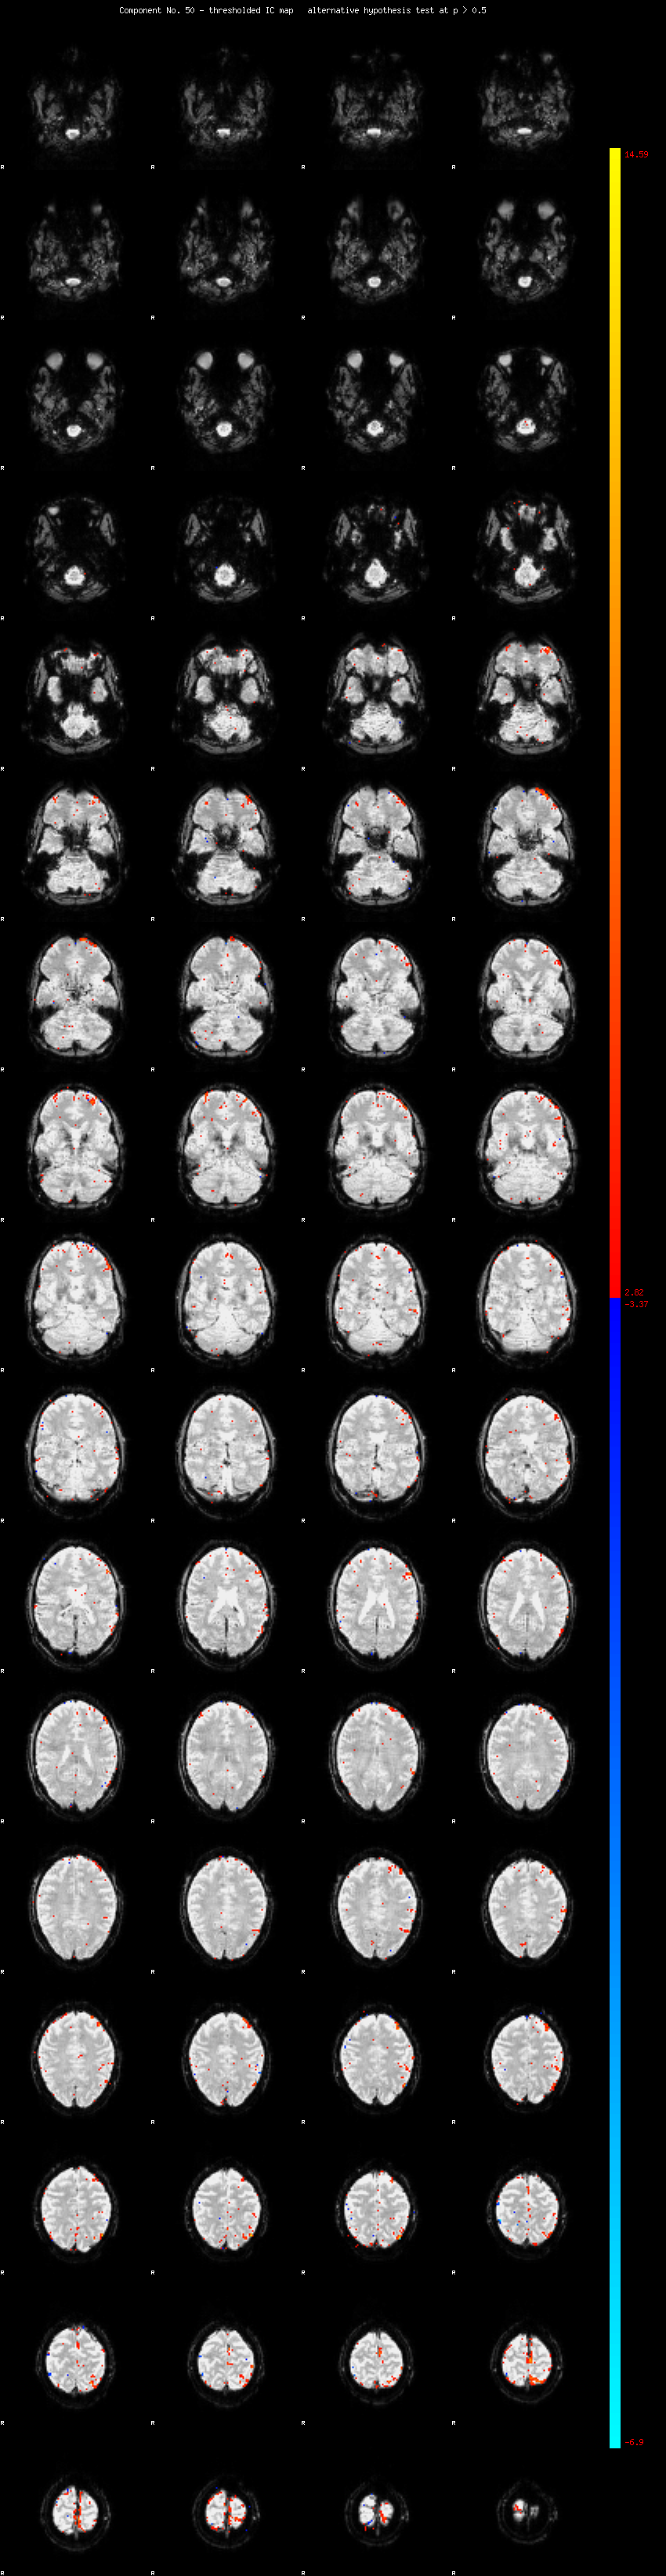

MELODIC Component 50

0.97 % of explained variance;     0.64 % of total variance

MMfit